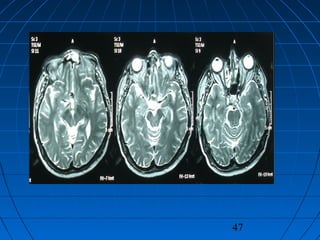

 56 yaşında erkek hasta56 yaşında erkek hasta

 BaşağrısıBaşağrısı (kronik-progresif, yaklaşık bir(kronik-progresif, yaklaşık bir

yıldır)yıldır)

 Nörolojik bakımdan normalNörolojik bakımdan normal

 Kranyal MRG:Kranyal MRG:

 pitüiter macroadenompitüiter macroadenom

 insidental AComA anevrizmasıinsidental AComA anevrizması

47

CERRAHİCERRAHİ

 Sol pterional trans-sylvian yaklaşımSol pterional trans-sylvian yaklaşım

 AcomA Anevrizması kliplendiAcomA Anevrizması kliplendi